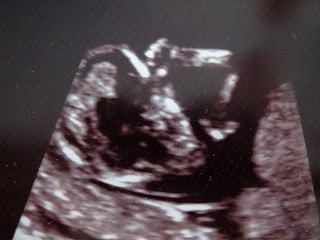

This is our first major ultrasound. Notice the 3D shots - very fancy :)

Meanwhile, nerve cells are multiplying rapidly, and in your baby's brain, synapses are forming furiously. His face looks unquestionably human: His eyes have moved from the sides to the front of his head, and his ears are right where they should be. From crown to rump, your baby-to-be is just over 2 inches long (about the size of a lime) and weighs half an ounce.